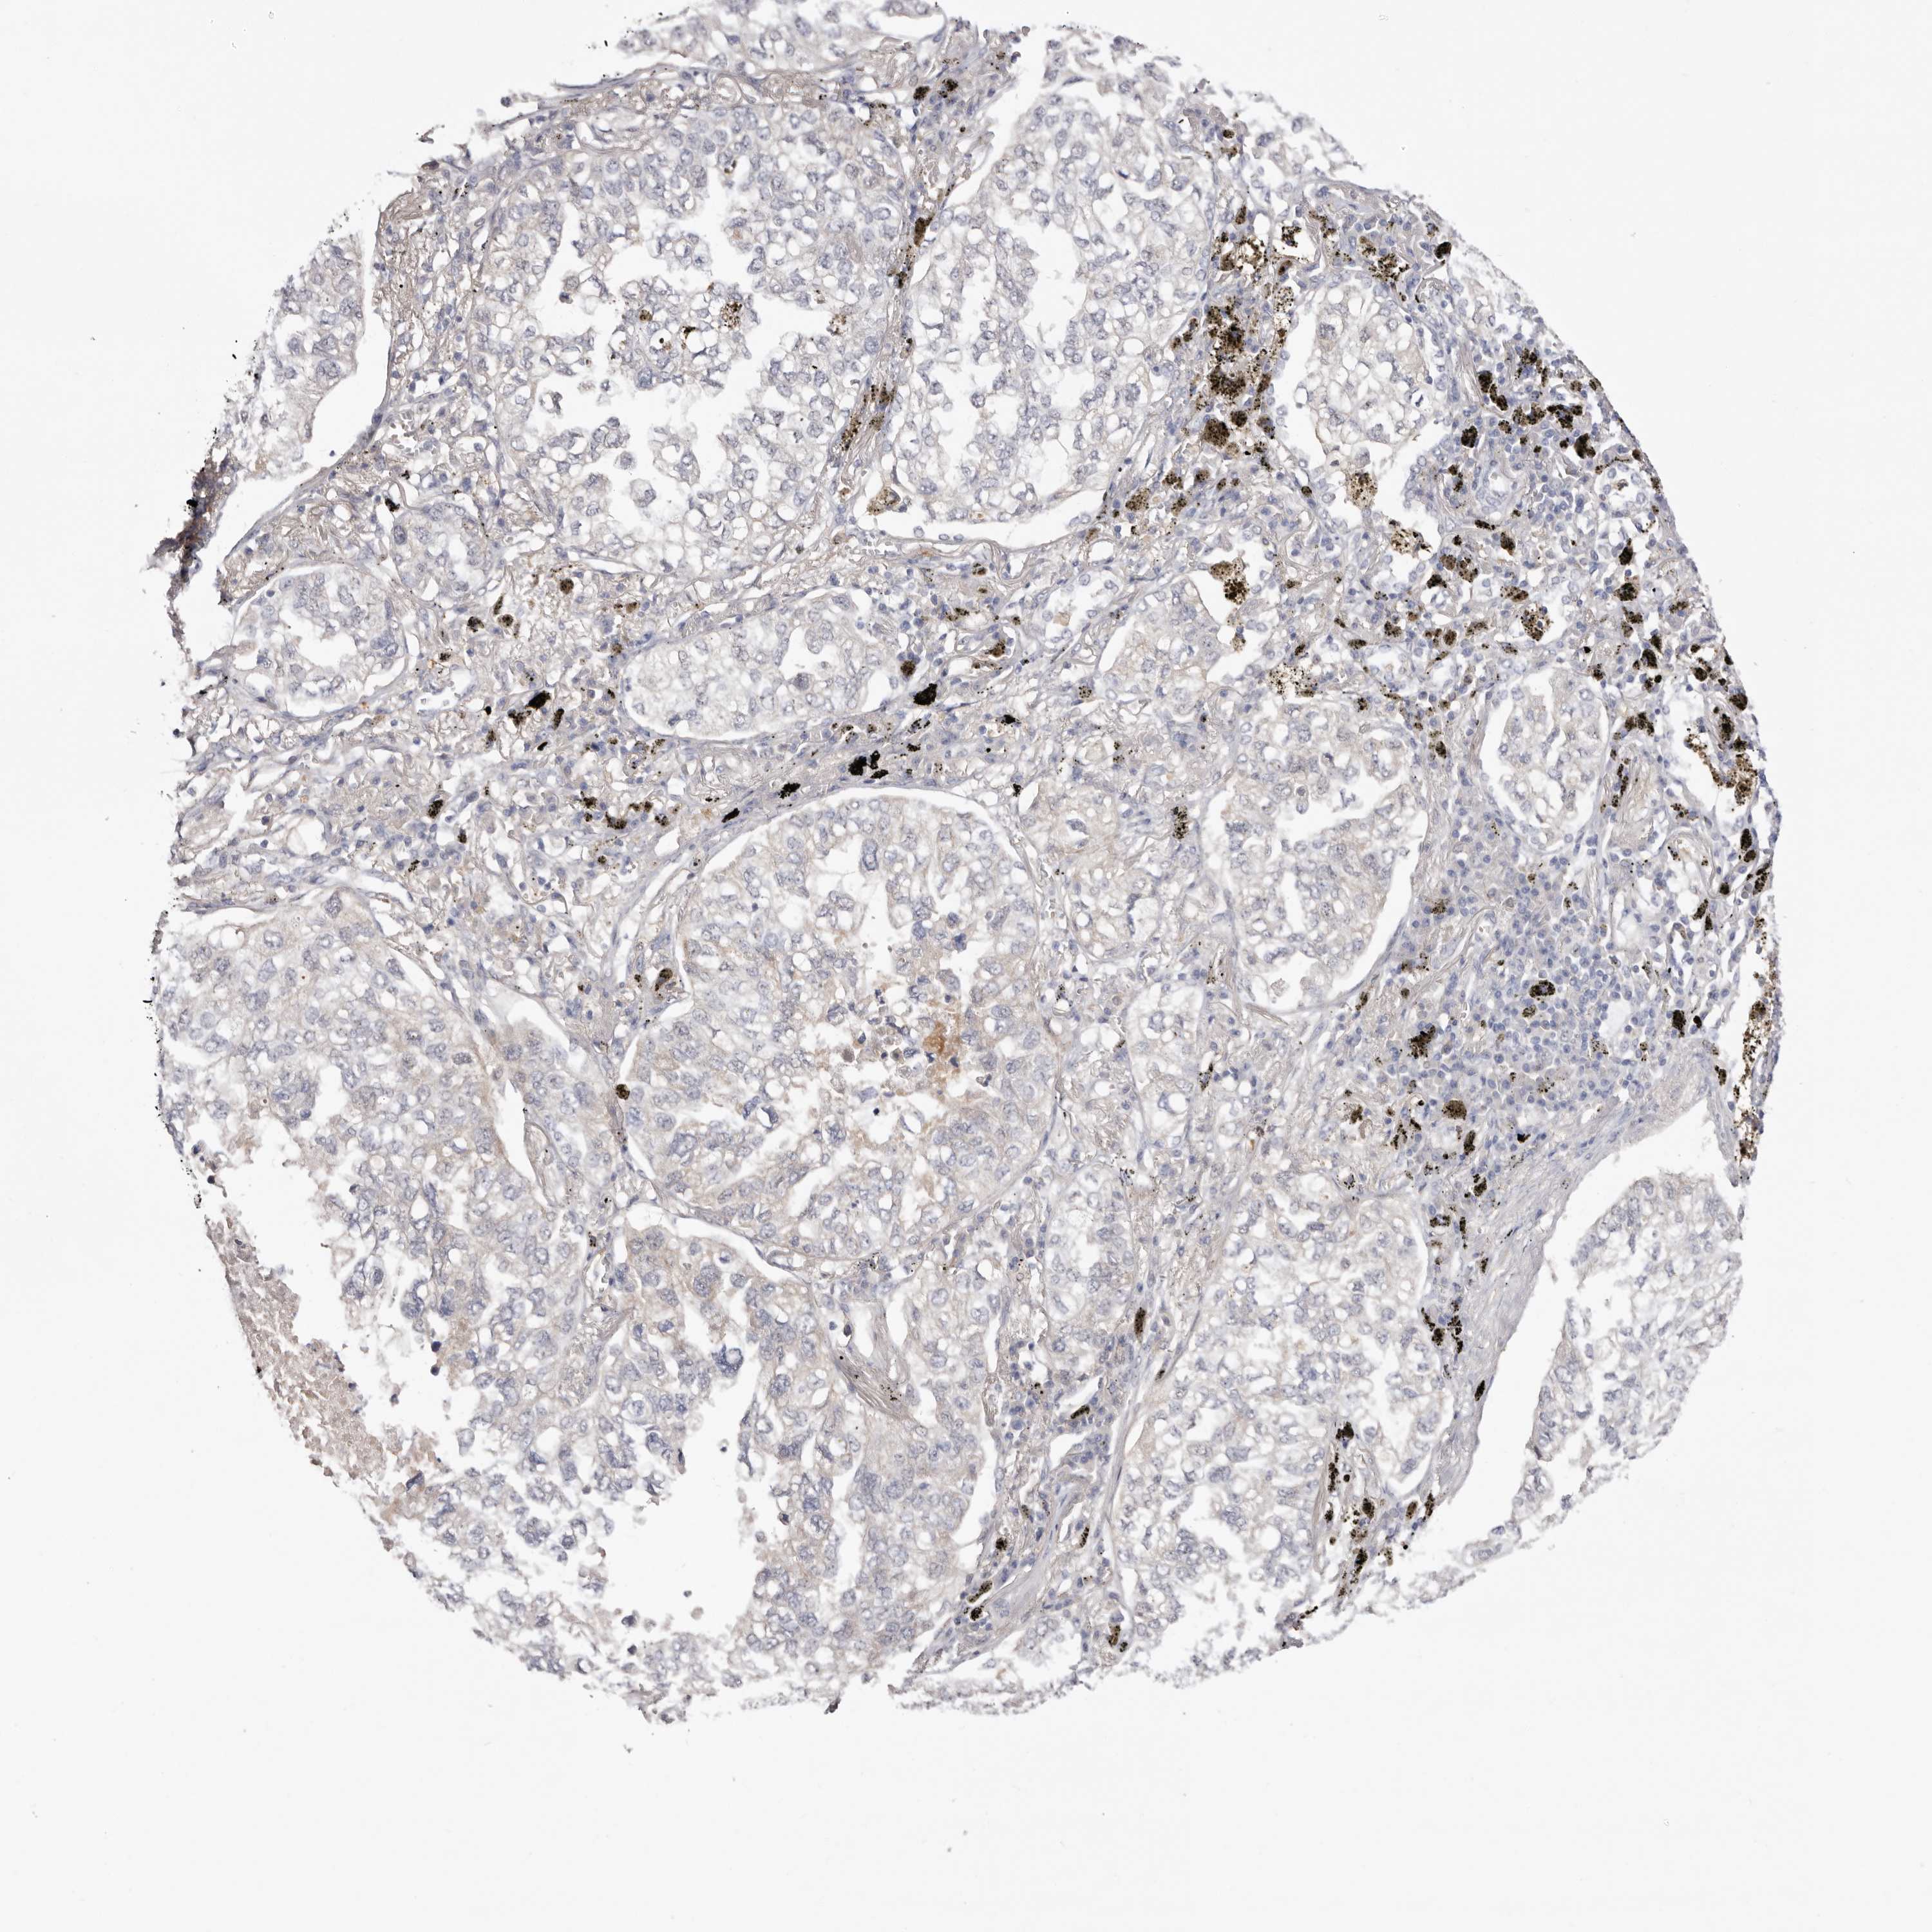

CANCER LUNG CANCER Show tissue menu

LUAD TCGA LUAD VALIDATION LUSC TCGA LUSC VALIDATION PROTEIN LUAD CPTAC PROTEIN LUSC CPTAC PROTEIN EXPRESSION